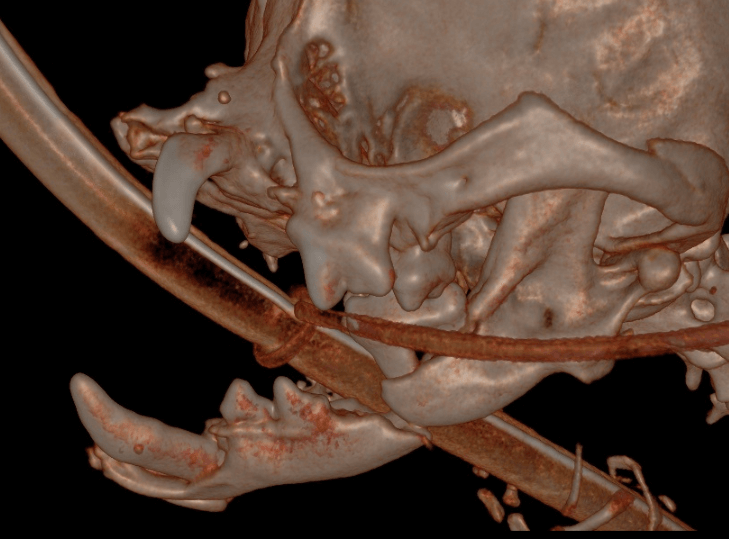

(Hover over image to read caption)

Demonstrates fracture site mobility before surgery

Coley Kay is severely brachycephalic and already had an almost ‘flat face.’ The fractures were present at the mid to caudal mandible at each lower first molar.

Bilateral mandibulectomy through the fracture sites along with removal of the diseased teeth. Coley Kay presented with only 7 of the 42 teeth remaining. Four of those 7 teeth were the structural, important teeth, yet all 7 were diseased beyond repair. The upper canine had a communication between the nose and the mouth (oral nasal fistula). All teeth remaining were removed and the small thin mandible portions were removed from the fracture sites forward. A cosmetic closure while rebuilding the lip vestibule to aid in retaining saliva was performed. The tongue will hang out, but it had done so often prior to the fall.